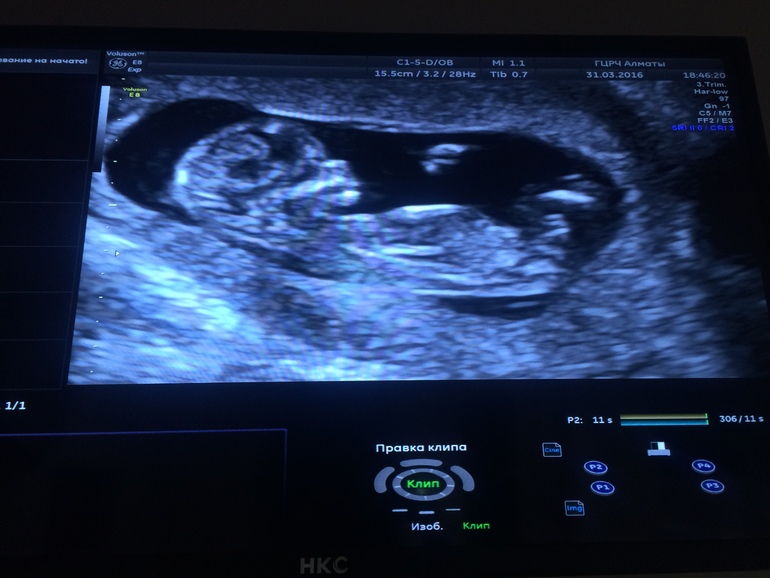

Перед зачатием у меня был гормональный сбой и месячные шли как попало, вообщем не высчитать. Последний раз мои месячные были в декабре... Вот знаю одно - 1 апреля на УЗИ сказали 13 недель и 0 дней.

Было похоже, что мальчик, как сказал врач, а так девчушку хочется...